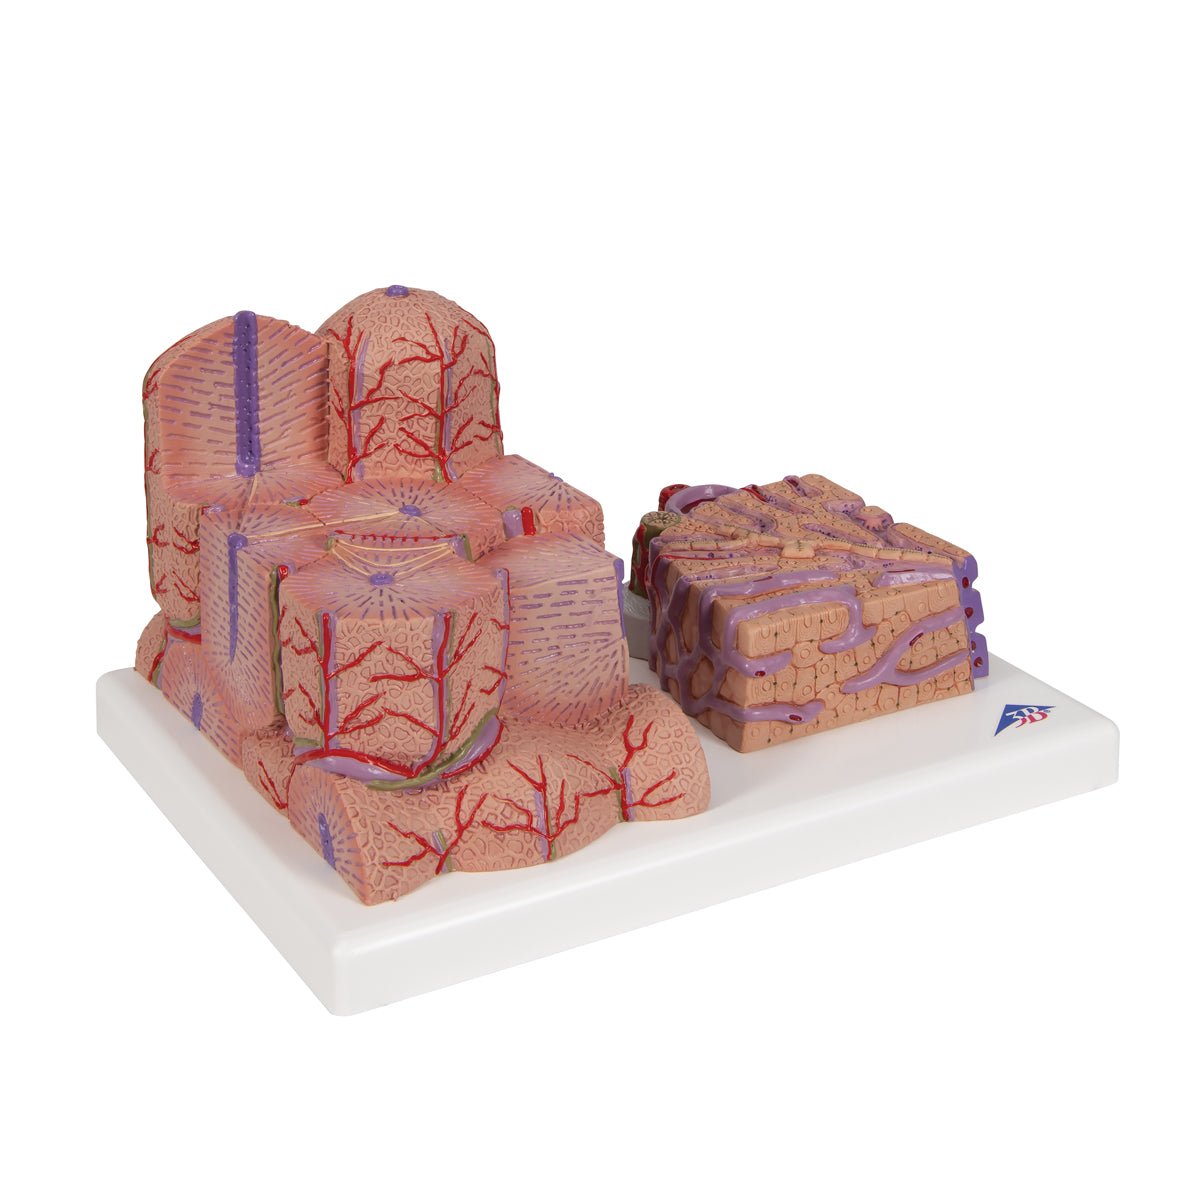

Salg af anatomiske modeller er det bærende element i eAnatomi, selvom vi også bruger mange ressourcer på at udvikle vores egne anatomiske materialer som fx plakater. Anatomiske modeller anvendes til forskellige formål og kan både vise afgrænset væv, organer samt organsystemer. Søger du en simpel model af knoglevæv eller måske en avanceret torso-model baseret på MRI teknologi, kan du finde det hele på eanatomi.com.